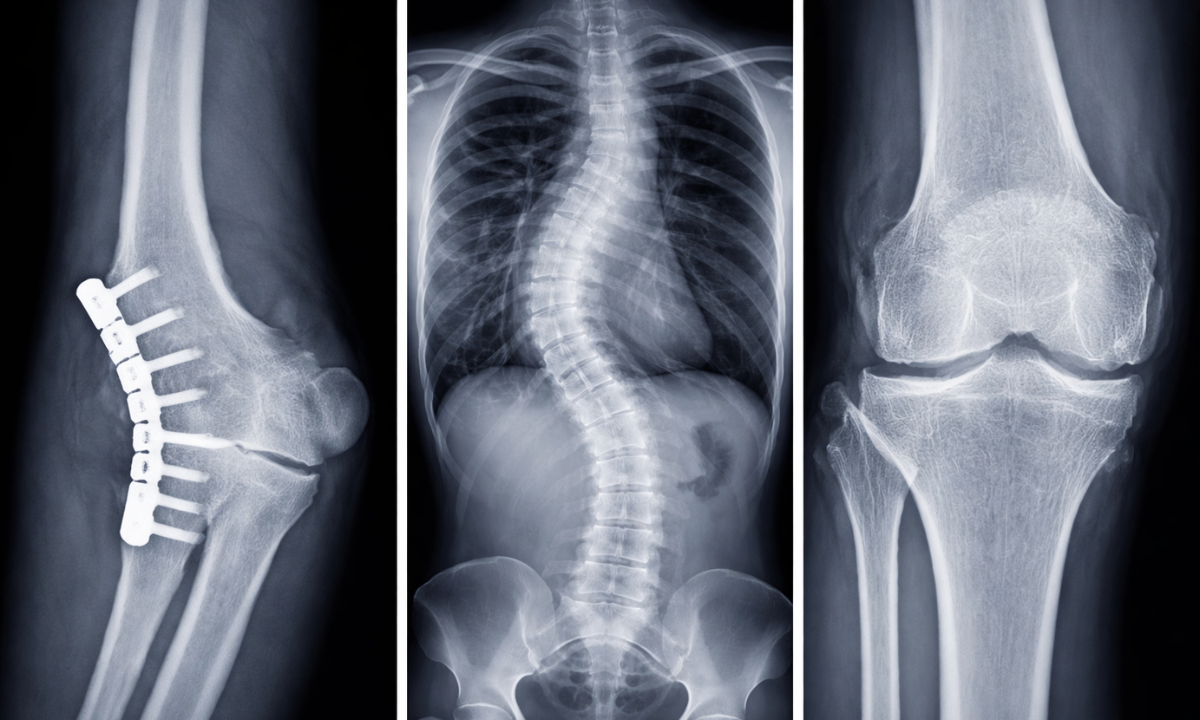

Skeletal and Spine Radiography

X-rays are the gold standard for assessing the skeletal system.

- Fractures: A simple X-ray can confirm the type and severity of a bone break.

- Spine: A spine X-ray is crucial for diagnosing scoliosis (curvature of the spine), herniated discs, or spinal stenosis. It helps doctors visualize the alignment of the vertebrae.

- Joints: It detects signs of arthritis, dislocations, or bone spurs.

For a spine X-ray, multiple views (front, side, and bending) are often taken to assess the stability of the spinal column under different movements.

This helps orthopedic surgeons plan treatments effectively.